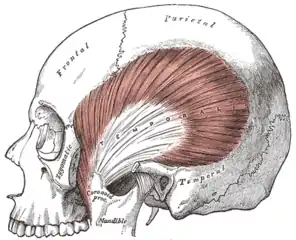

- Hypertrophy of the muscles of mastication (increase in the size of the muscles that move the jaw),[11] particularly the masseter muscle.[10][9][12]

- Headaches, particularly pain in the temples,[5] caused by muscle pain associated with the temporalis muscle.

Bruxism is usually detected because of the effects of the process (most commonly tooth wear and pain), rather than the process itself. The large forces that can be generated during bruxism can have detrimental effects on the components of masticatory system, namely the teeth, the periodontium and the articulation of the mandible with the skull (the temporomandibular joints). The muscles of mastication that act to move the jaw can also be affected since they are being utilized over and above of normal function.[1]

The muscles of mastication (the temporalis muscle, masseter muscle, medial pterygoid muscle and lateral pterygoid muscle) are paired on either side and work together to move the mandible, which hinges and slides around its dual articulation with the skull at the temporomandibular joints. Some of the muscles work to elevate the mandible (close the mouth), and others also are involved in lateral (side to side), protrusive or retractive movements. Mastication (chewing) is a complex neuromuscular activity that can be controlled either by subconscious processes or by conscious processes. In individuals without bruxism or other parafunctional activities, during wakefulness the jaw is generally at rest and the teeth are not in contact, except while speaking, swallowing or chewing. It is estimated that the teeth are in contact for less than 20 minutes per day, mostly during chewing and swallowing. Normally during sleep, the voluntary muscles are inactive due to physiologic motor paralysis, and the jaw is usually open.[20]

Some bruxism activity is rhythmic with bite force pulses of tenths of a second (like chewing), and some have longer bite force pulses of 1 to 30 seconds (clenching). Some individuals clench without significant lateral movements. Bruxism can also be regarded as a disorder of repetitive, unconscious contraction of muscles. This typically involves the masseter muscle and the anterior portion of the temporalis (the large outer muscles that clench), and the lateral pterygoids, relatively small bilateral muscles that act together to perform sideways grinding.